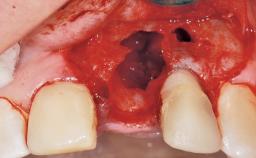

Immediate Flapless Placement of an Implant in a Maxillary Left Central Incisor Site

A 42-year-old female patient was referred to our clinic at the School of Dentistry of the University of São Paulo in November 2004, presenting a deficient restoration in the upper left central incisor. The clinical examination revealed no gingival retraction or any signs of gingival inflammation and, therefore, previous periodontal treatment was not considered. The patient presented a high lip line at full smile and a thin tissue biotype. This combination characterized a high-risk situation from an anatomic point of view, which required careful preoperative planning and cautious surgical execution.

Soft Tissue Anatomy Intact Defective

Socket Integrity Sufficient, with intact bone walls

Bone Volume Sufficient, with intact walls